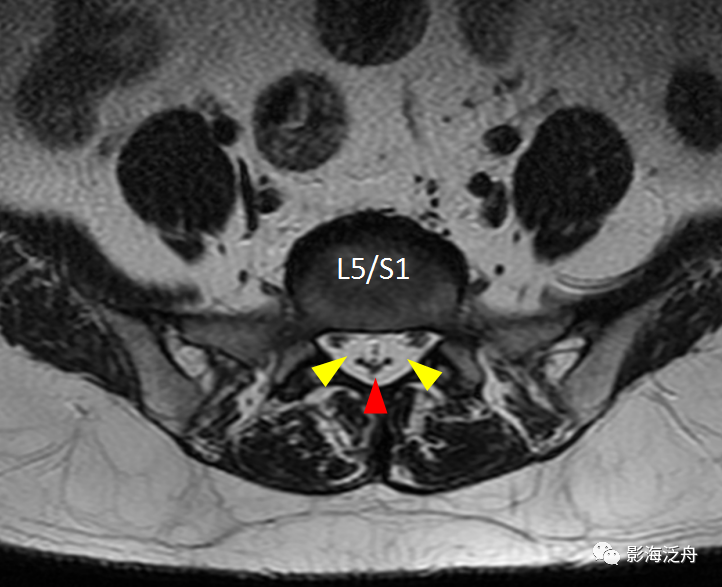

正常的腰骶部MR解剖:一般情况下,L5/S1层面是常规腰椎MR平扫横断位的最后一层,如上图所示,硬膜囊(红箭头)外只有很少量的脂肪(黄箭头)分布,马尾神经由硬膜囊内(绿箭)穿出并沿椎间孔区向外走行(蓝箭)。硬膜囊内的马尾神经均匀分散在硬膜囊边缘区。

开篇那个患者的L5/S1水平横断面图像:可见椎管内大部分空间被脂肪组织占据(黄箭头),硬膜囊显著受压呈“V字”形改变(红箭头),硬膜囊内的马尾神经聚拢在一起显示不清。